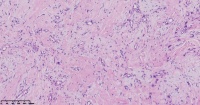

手指包块

性别

女

年龄

39岁

临床诊断

一般病史

标本名称

大体所见

皮赘。

不考虑神经来源?